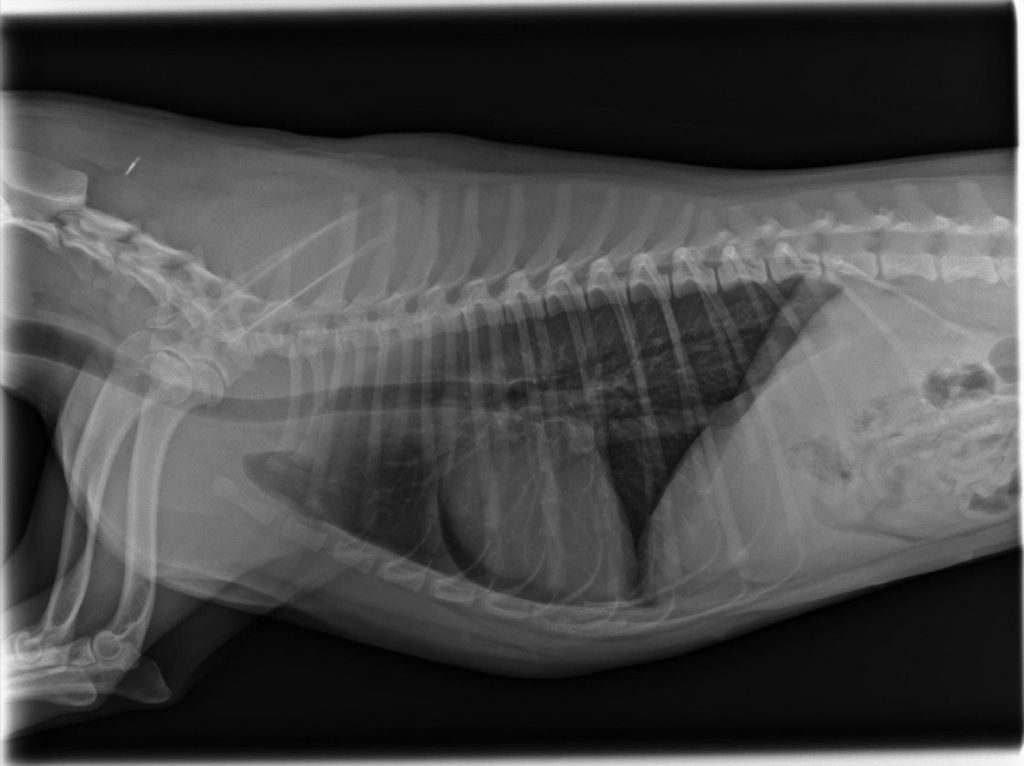

강아지가 목줄을 하고 산책 중에 갑자기 집에 가려고 차도로 뛰어드는바람에 교통사고가 났습니다. 천천히 달려오는 차에 부딪히기는 했지만 걱정돼서 바로 병원으로 갔고 엑스레이, 초음파, 혈액검사 다 시행했지만 이상이 없다고 얘기했습니다. 그런데 사고 이후로 계속 토를 해서 병원에 가서 구토약이랑 진통제를 받아와서 먹였는데도 계속 구토를 하네요ㅠ 사료를 그대로 토하는데 이게 스트레스때문인지 아니면 검사상에 이상이 있는지 여쭤보고 싶어서 글 남깁니다. 또한 가슴쪽을 부딪혔는데 흉부 엑스레이 상에서 이상소견이 있는지 확인 좀 부탁드립니다.

흉부 엑스레이상에서는 교통사고와 관련한 특별한 이상이 관찰되지 않습니다.